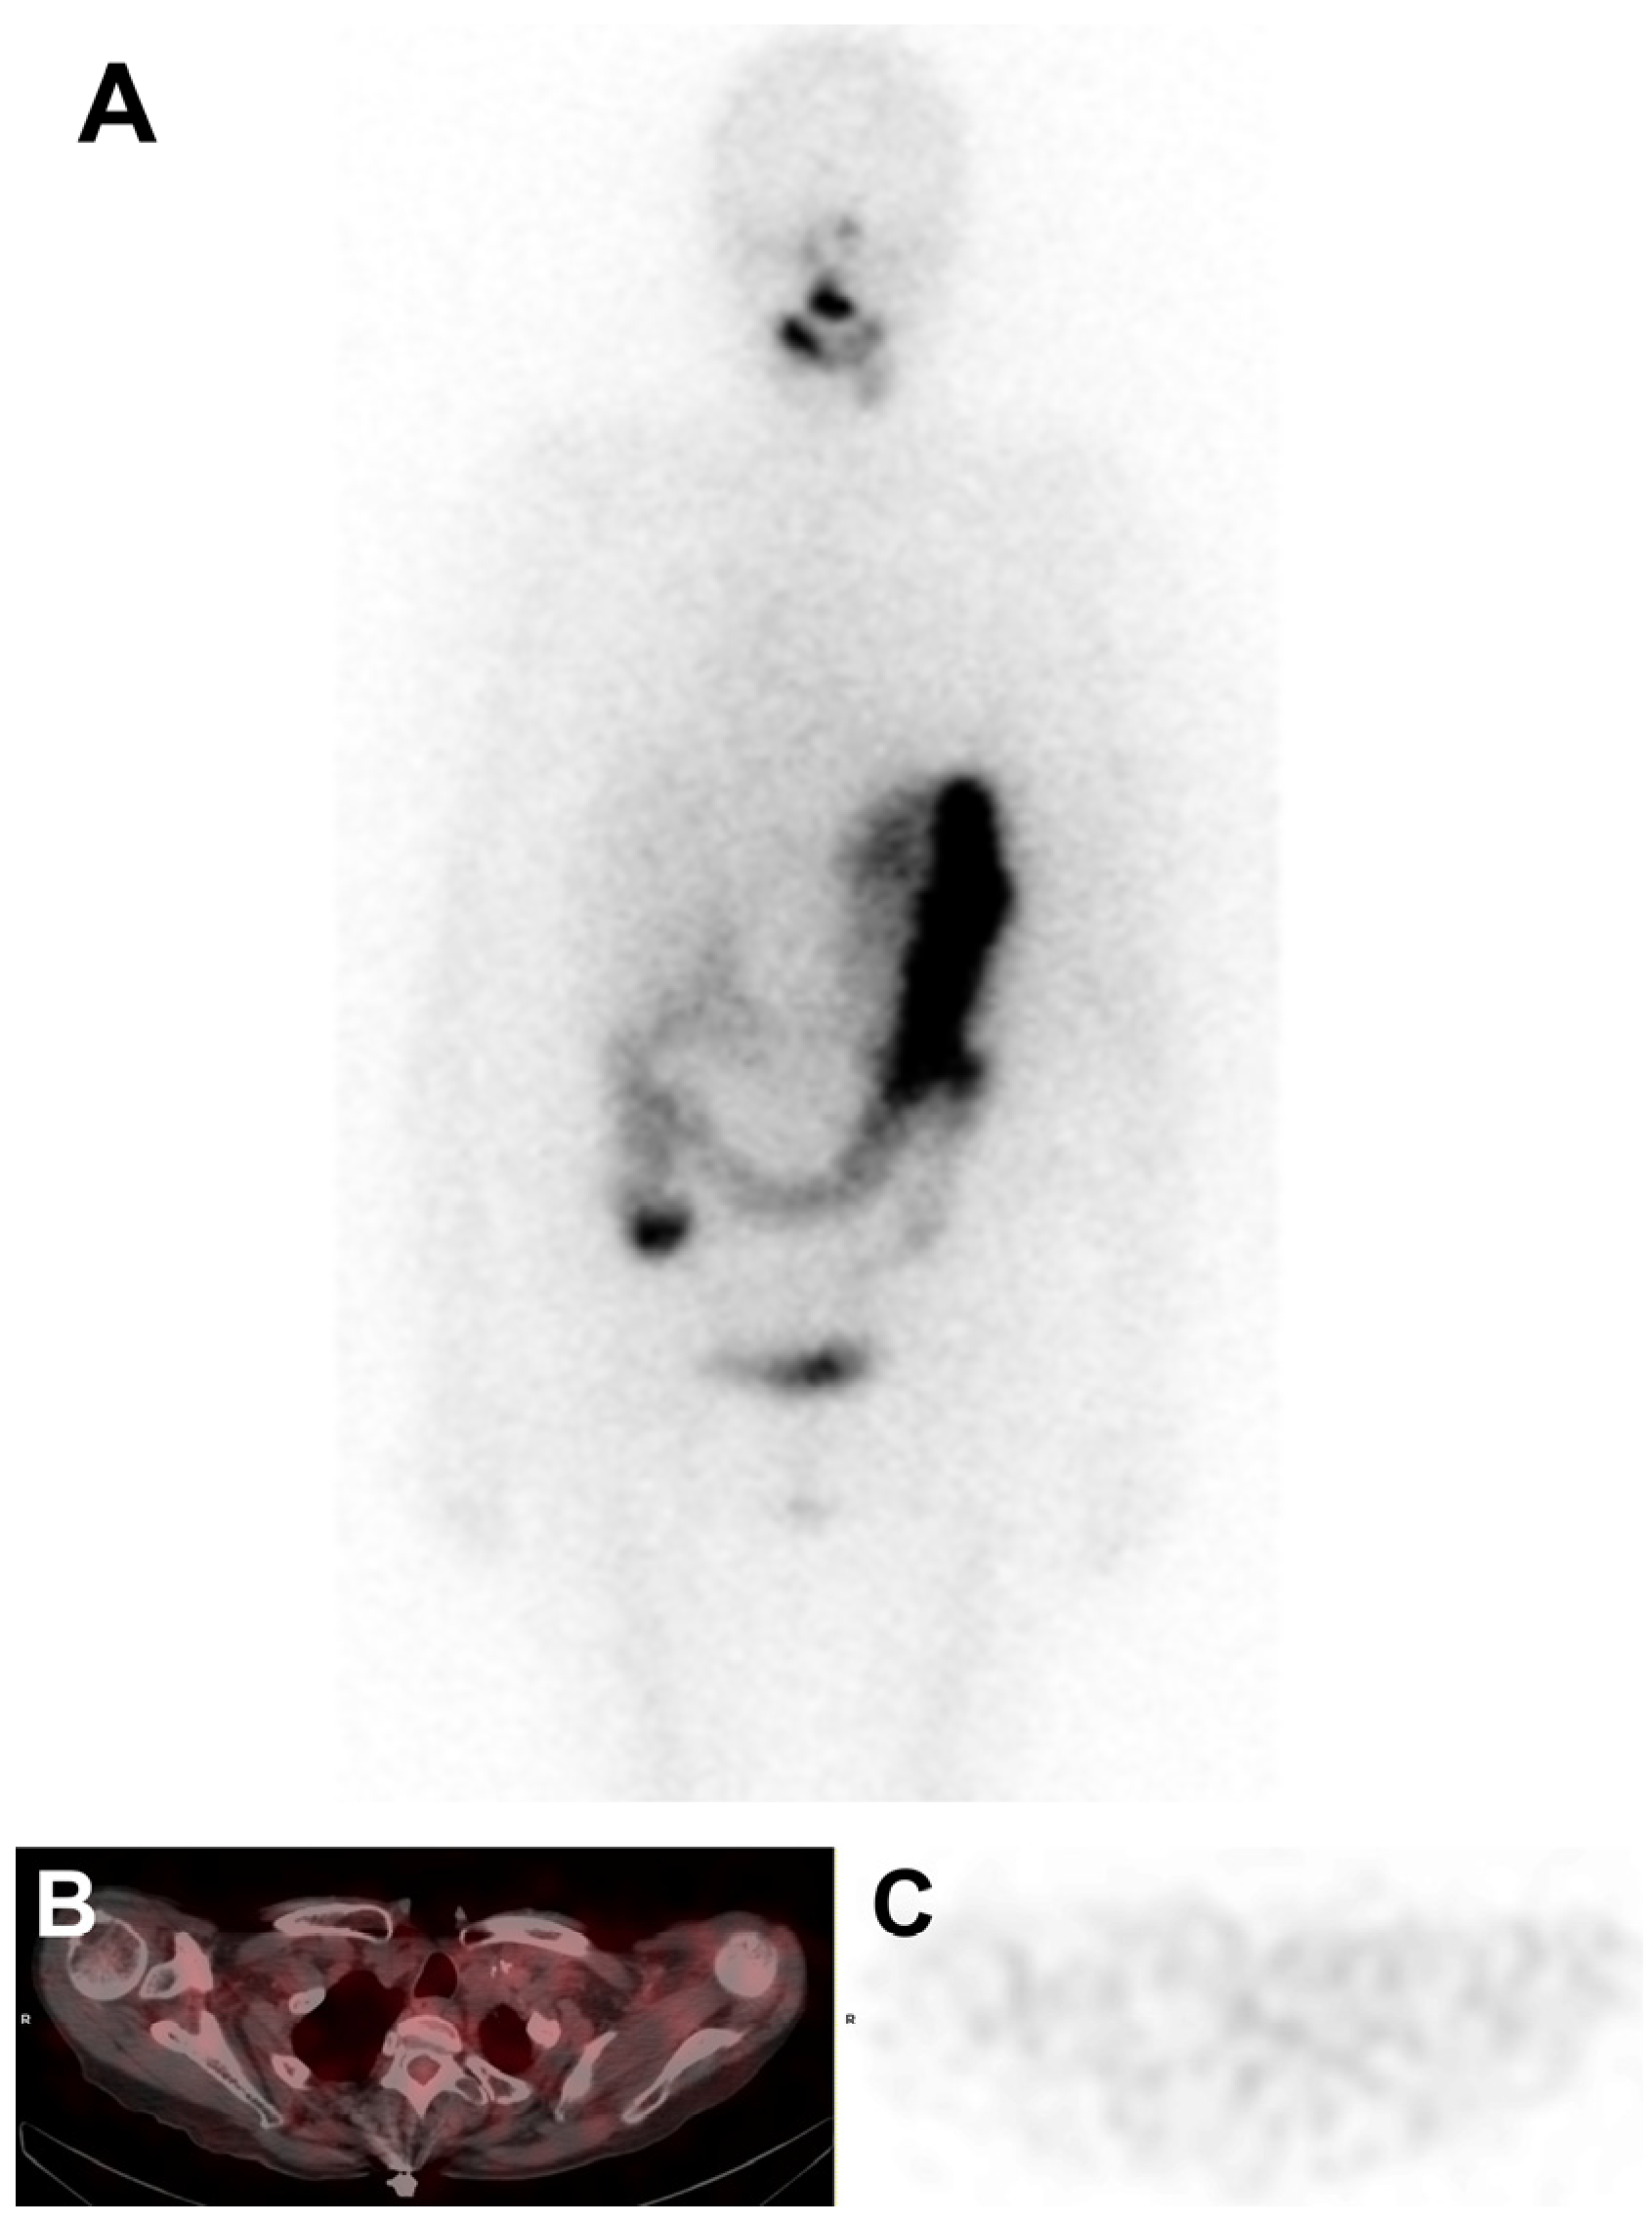

2. Case Presentation

- Balakirouchenane, D.; Seban, R.; Groussin, L.; Puszkiel, A.; Cottereau, A.S.; Clerc, J.; Vidal, M.; Goldwasser, F.; Arrondeau, J.; Blanchet, B.; et al. Pharmacokinetics/Pharmacodynamics of Dabrafenib and Trametinib for Redifferentiation and Treatment of Radioactive Iodine-Resistant Mutated Advanced Differentiated Thyroid Cancer. Thyroid Off. J. Am. Thyroid Assoc. 2023, 33, 1327–1338. [Google Scholar] [CrossRef]

- Rothenberg, S.M.; McFadden, D.G.; Palmer, E.L.; Daniels, G.H.; Wirth, L.J. Redifferentiation of Iodine-Refractory BRAF V600E-Mutant Metastatic Papillary Thyroid Cancer with Dabrafenib. Clin. Cancer Res. 2015, 21, 1028–1035. [Google Scholar] [CrossRef] [PubMed]

- Jaber, T.; Waguespack, S.G.; Cabanillas, M.E.; Elbanan, M.; Vu, T.; Dadu, R.; Sherman, S.I.; Amit, M.; Santos, E.B.; Zafereo, M.; et al. Targeted Therapy in Advanced Thyroid Cancer to Resensitize Tumors to Radioactive Iodine. J. Clin. Endocrinol. Metab. 2018, 103, 3698–3705. [Google Scholar] [CrossRef] [PubMed]